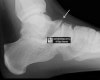

X-ray : 거골 부리(Talar beak)

Cf) 거골 부리(Talar beak)

거골 경부의 배측에 생기는 골극입니다.

Congenital tarsal coalition에 합병되는 경우가 많고, 압박하지 않으면 증상이 없습니다.

치료를 필요로 하는 경우는 드뭅니다.